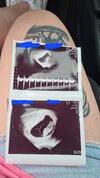

Wszystko jest dobrze. Byłam bardzo zdenerwowana a nie potrzebnie. To mój mały człowieczek. Ale się cieszę ☺️☺️☺️☺️☺️☺️

Załączniki

• IMG-20220713-WA0004.jpeg

IMG-20220713-WA0004.jpeg

1,7 MB · Wyświetleń: 135

Cudownie <3 2,5 cm to już nie taki mały!